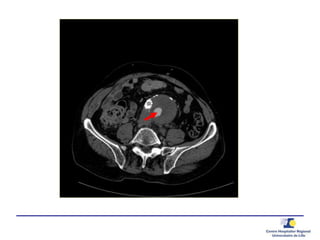

Ponction translombaire –

embolisation directe

Ponction

Anévrysmographie